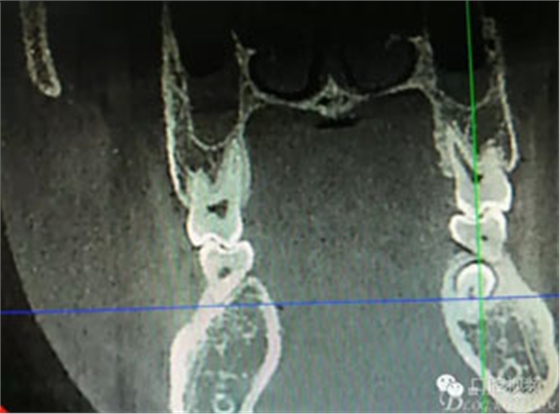

圖2.術(shù)前的CBCT,35移位至36、37之間的舌側(cè)。